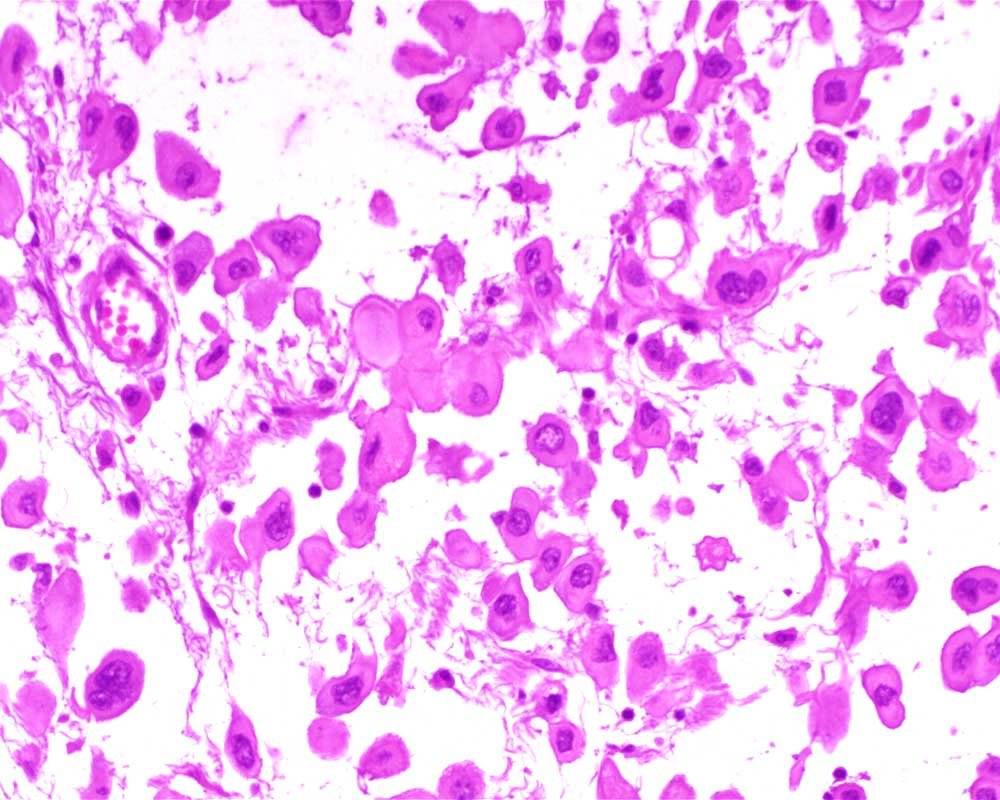

Case: PeritonealLesion

Final Diagnosis: